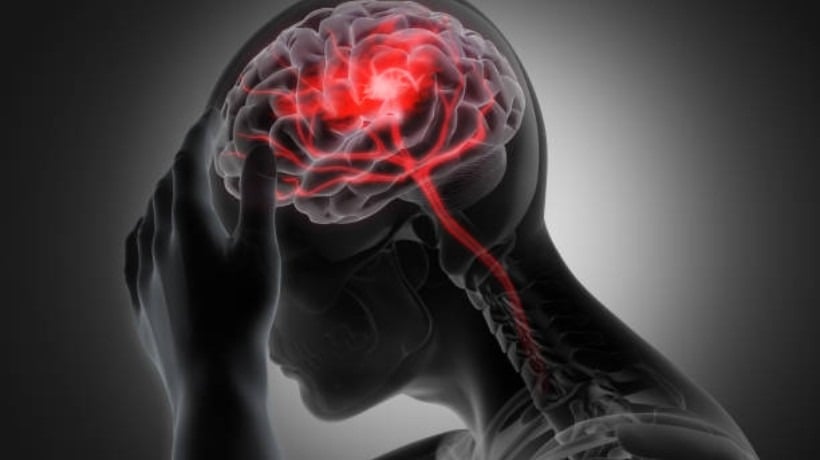

40% de los ingresos por urgencias en Clínica Bupa Antofagasta corresponden a accidentes cerebrovasculares

Especialistas advierten que la falta de información para detectar los primeros síntomas y los factores de riesgo sigue siendo una de las principales barreras para actuar a tiempo frente a un accidente cerebrovascular (ACV).